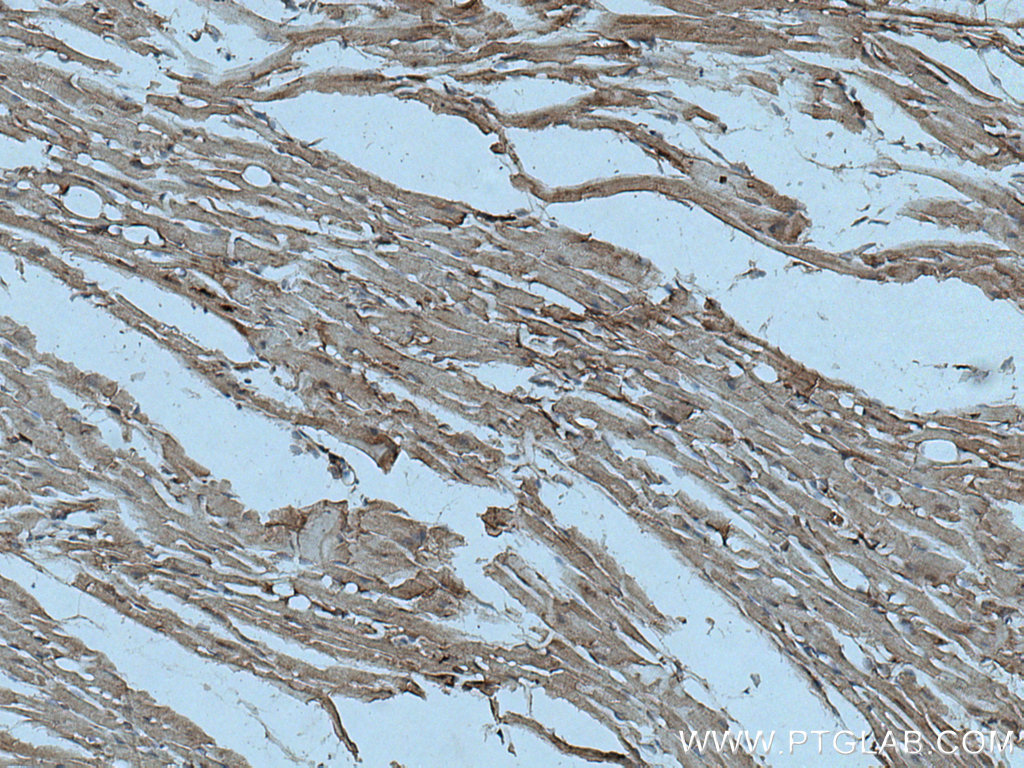

| Positive IHC detected in | human pancreas cancer tissue, mouse heart tissue Note: suggested antigen retrieval with TE buffer pH 9.0; (*) Alternatively, antigen retrieval may be performed with citrate buffer pH 6.0 |

| Immunohistochemistry (IHC) | IHC : 1:200-1:800 |